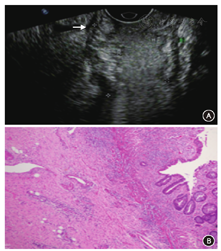

2.不同位置直肠癌的超声诊断结果与病理结果对照(表2)。低、中位直肠癌超声诊断的kappa值分别为0.27,0.63,高位直肠癌因例数太少无法统计kappa值,其准确率为100%。直肠腔内超声诊断对于中高位直肠癌的一致性较好,而低位的一致性差,而且出现T分期低估的比例较高达33.3%。超声诊断比照病理结果,出现低估和高估的图像(图1,图2)。

本研究中出现不同程度分期过高或过低,其中以低估较多(21例,24.4%),与文献不同[12]。回顾图像发现21例低估患者中,均为小病灶,范围在1~2 cm,可能由于病灶较小,加上新辅助治疗后,局部组织间质纤维化、组织变性,直肠壁结构紊乱,影响超声对病灶的结构分辨力[13](图1)。高估7例(8.1%,7/86),回顾图像发现,可能与病灶部位的病理改变有关,病理变化多提示为重度放疗反应,在镜下呈黏液湖、大量炎性细胞浸润(图2),超声图像中肠壁黏膜层增厚、肌层与直肠系膜分界不清,误以为是肿瘤浸润。